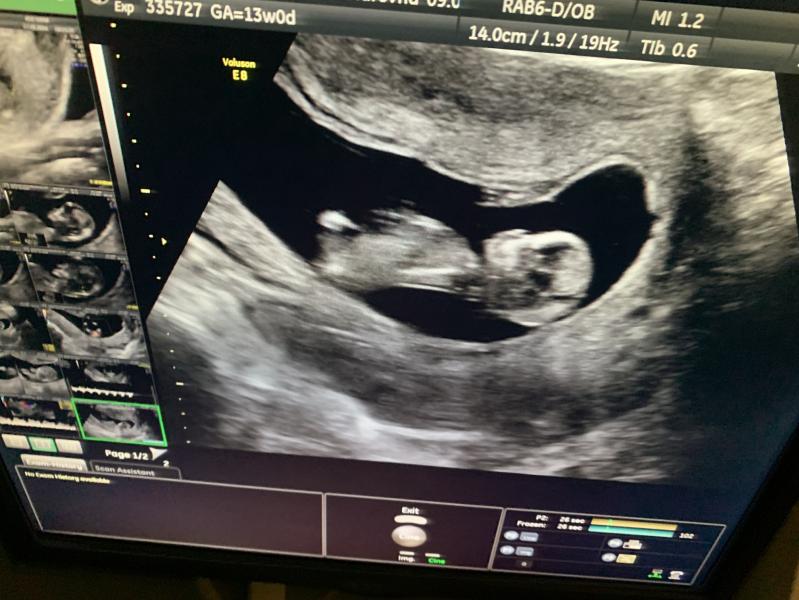

Вчера мы прошли первый скрининг😍🤰🏻🤍 Все отлично! Малышок сильно активничал, прыгал во всю, за этим было очень мило наблюдать) Дали снять видео) В понедельник сдала кровь на определение пола, на скрининге предположили девчушку, но срок еще маленький совсем, так что ждемс результаты крови❤️